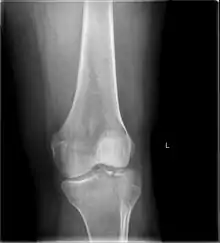

A tibial plateau fracture is a break of the upper part of the tibia (shinbone) that involves the knee joint.[1] Symptoms include pain, swelling, and a decreased ability to move the knee.[1] People are generally unable to walk.[2] Complication may include injury to the artery or nerve, arthritis, and compartment syndrome.[1]

The cause is typically trauma such as a fall or motor vehicle collision.[1] Risk factors include osteoporosis and certain sports such as skiing.[2] Diagnosis is typically suspected based on symptoms and confirmed with X-rays and a CT scan.[1] Some fractures may not be seen on plain X-rays.[2]